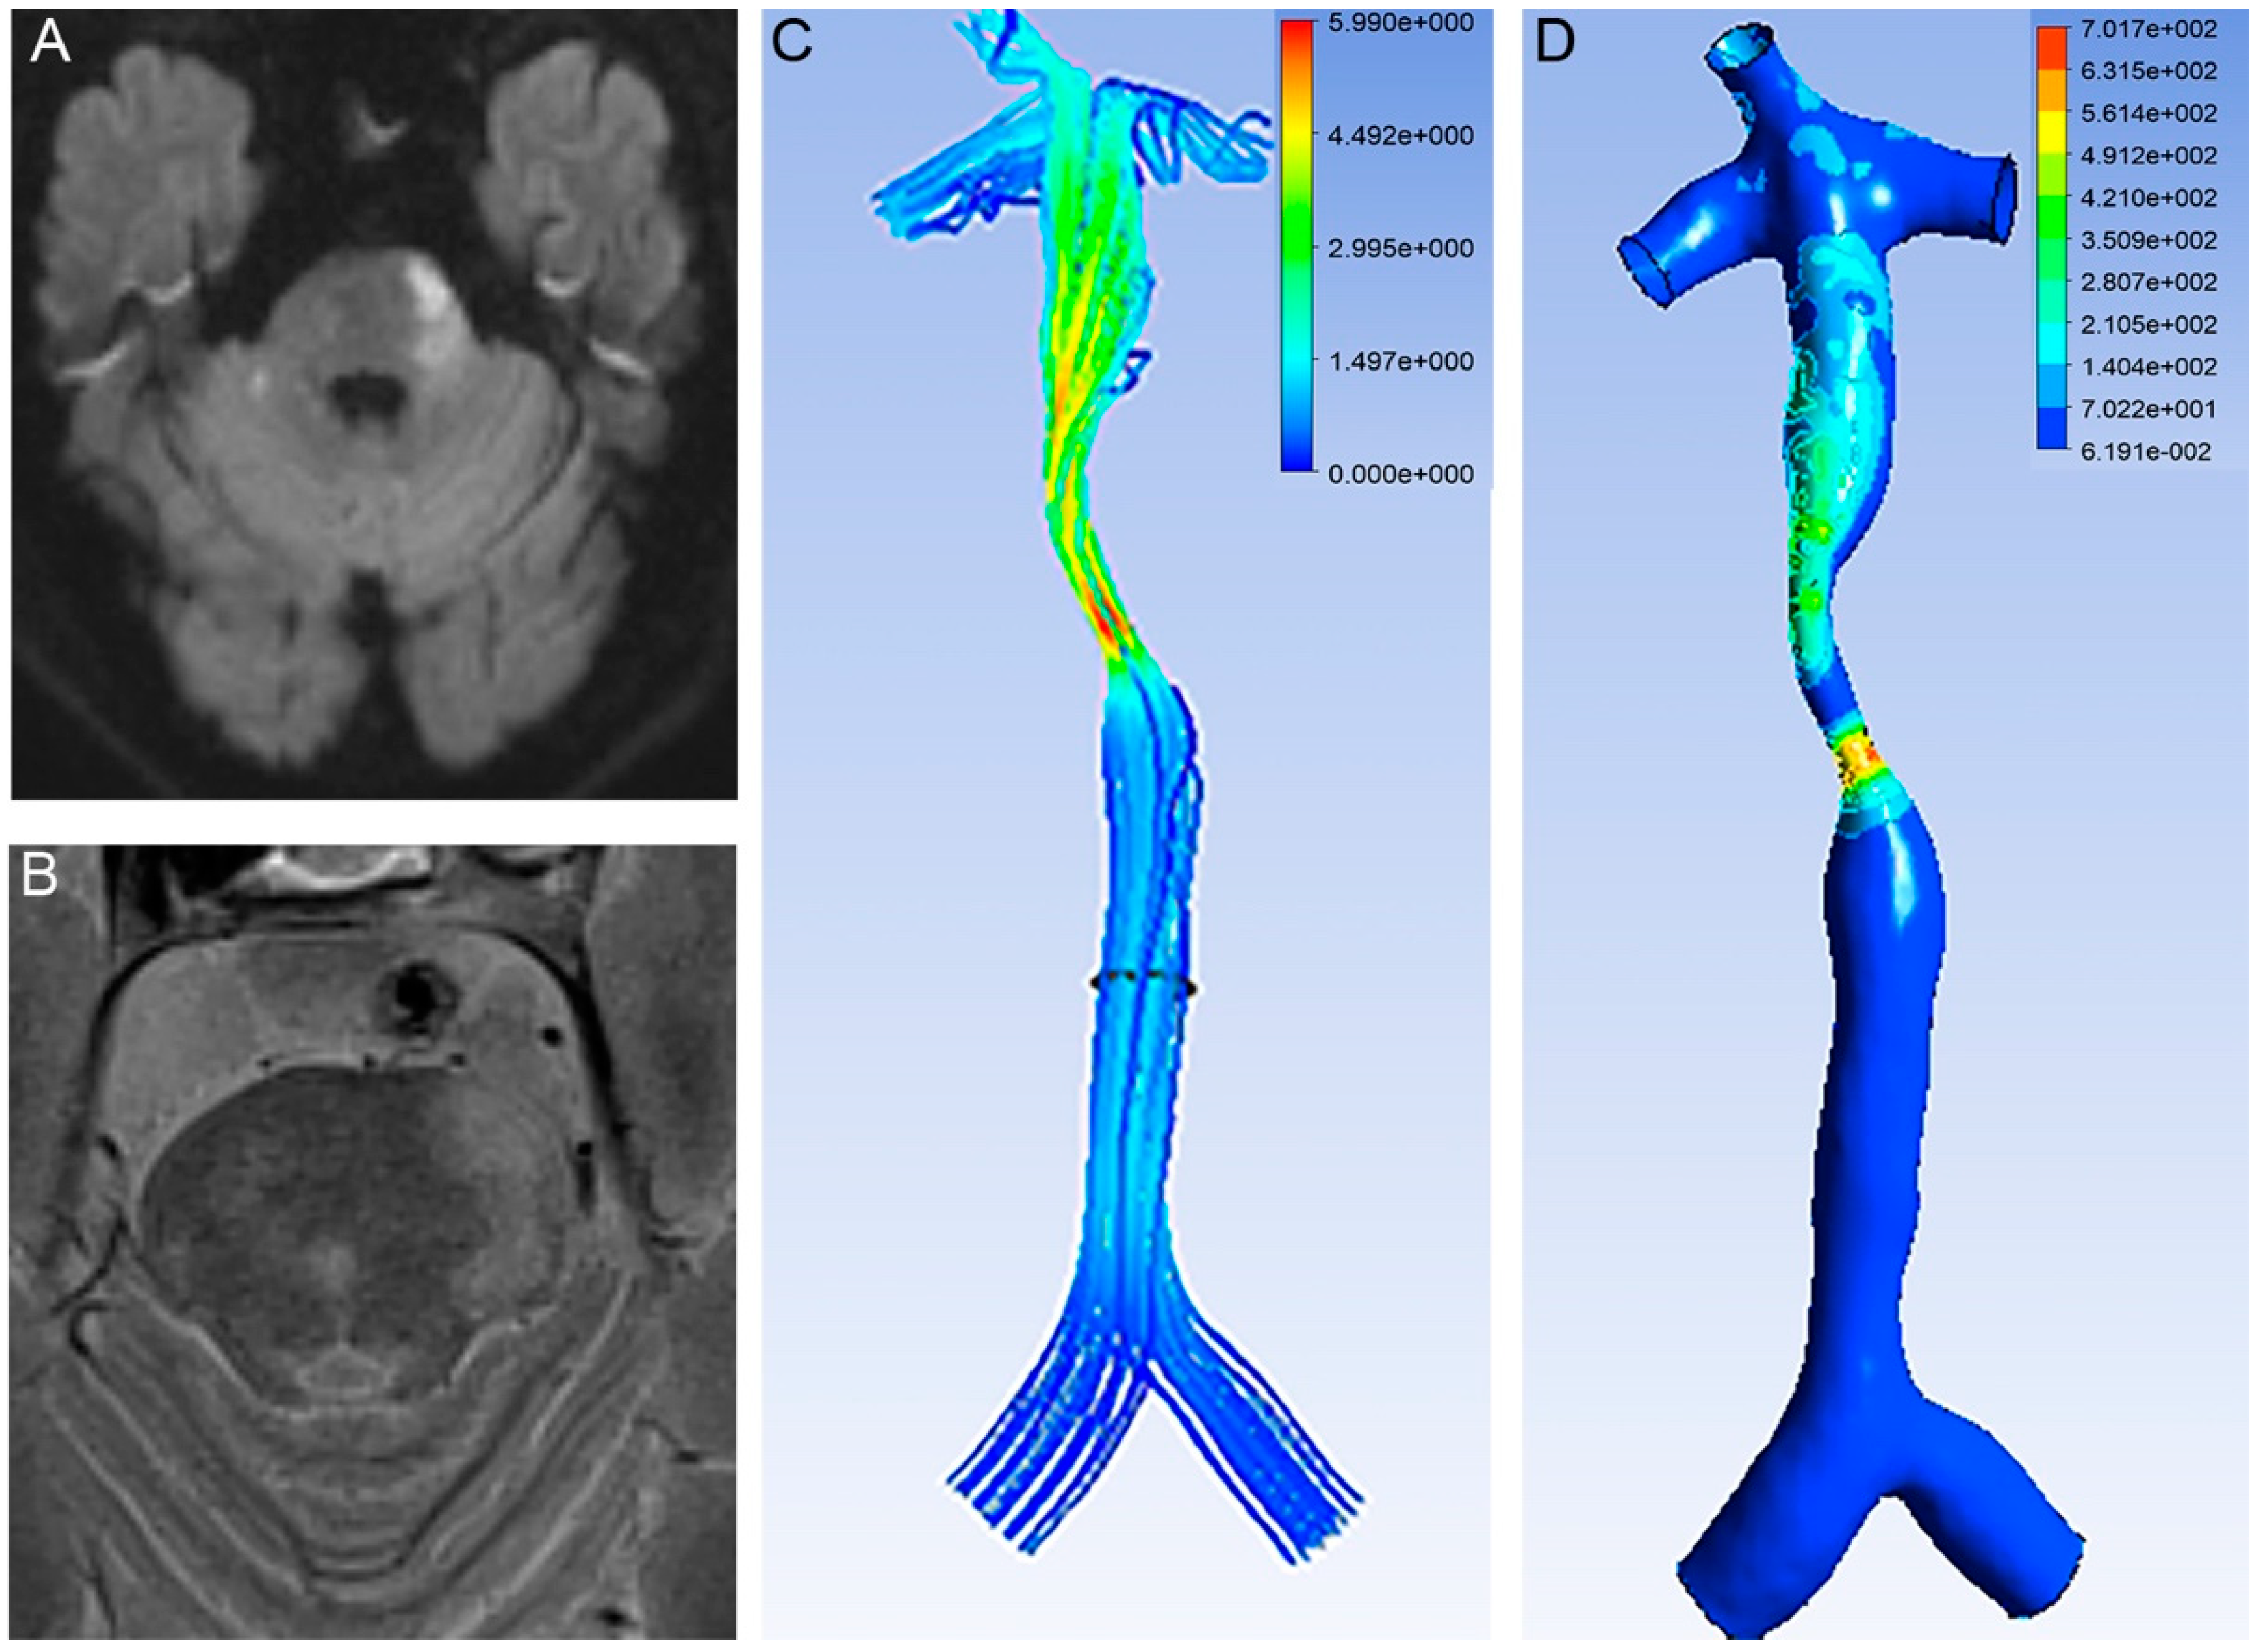

The stenotic WSS was measured at the most severely narrowed cross-section. The proximal WSS was measured at the normal vessel segment proximal to the plaque (Figure 1). The WSS ratio was defined as follows: WSS ratio = Stenotic WSS/ proximal WSS.

Figure 1.

No infarction occurred in the lower proximal WSS. (A) DWI showed no infarction. (B) T2 images of HR MRI showed intact fibrous cap. (C) T1 images of HR MRI showed intact fibrous cap. (D) T2 images of HR MRI showed intact fibrous cap. (E) Velocity of BA. The planes (gray and dark) represent the place we measured. (F) WSS of BA. Proximal WSS was 2.88 Pa and stenotic WSS was 490.78 Pa.

An RFC was identified in the 35 patients (19.9%, Figure 3). An RFC was significantly associated with acute infarction (27/35 vs. 96/141, p < 0.05, Table 1, Figure 1 and Figure 3).

Higher proximal WSS related with stroke. (A) DWI showed an infarction located in the pontine. (B) T2 images of HR MRI showed RFC. (C) Velocity of BA. (D) WSS of BA. Proximal WSS was 7.34 Pa and stenotic WSS was 559.51 Pa.

The proximal WSS was higher in the patients with an RFC than in those without an RFC (8.68 ± 17.60 vs. 8.07 ± 4.55, p < 0.05, Table 1). The multivariable logistic regression analysis showed that proximal WSS was an independent risk factor for RFC (1.564, 95% CI 1.101–2.222, p < 0.05, Table 2).

The cut-off value of the proximal WSS was 4.84 Pa (area under the ROC curve 0.732, p = 0.008, 95% CI 0.565–0.899). In one patient with a lower proximal WSS, there was no infarction (Figure 3).